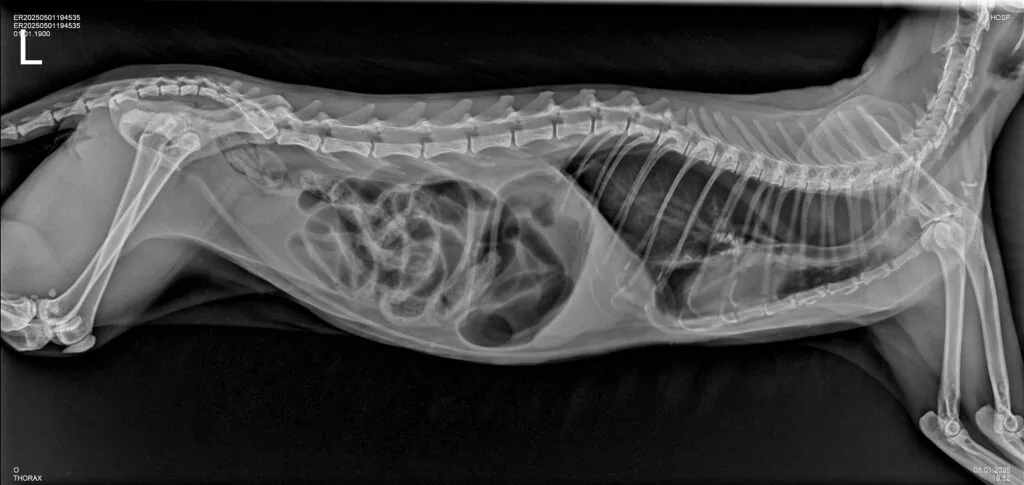

- Для определения патологий органов грудной клетки: легких, сердца, наличия инородных тел в пищеводе. Рентген-диагностика применяется при таких симптомах у животного, как: проблемы с дыханием, обусловленные наличием воспалительных процессов, новообразований, скоплением жидкости в легких (плевральный выпот); сердечная недостаточность, изменение размеров сердца, например его увеличение или кардиомегалия, пневмоторакс (скопление воздуха в грудной клетке), гидроторакс (скопление жидкости в грудной клетке).

- При патологиях органов брюшной полости: кишечной непроходимости, вызываемой обструкцией кишечника проглоченными животным инородными телами или при развитии новообразований/опухолей кишечника. Если животное проглотило несъедобный предмет (игрушку, кость и др), который не вышел естественным путем и вызвал обструкцию, застрял в пищеварительном тракте, рентген-диагностика будет показана в качестве методов исследования первого выбора в комплексе с УЗ-диагностикой, и даст ветеринарному врачу информацию о местоположении инородного тела, его размере и структуре, а также поможет определиться с тактикой лечения. В целях исключения инородного предмета/тел в желудочно-кишечном тракте животного применяется рентгенография с контрастным веществом, которая требует больших временных затрат и подготовки в виде применения у животного контрастного вещества, но чрезвычайно эффективна и распространена в ветеринарной практике.

- Для выявления заболеваний мягких тканей: признаки пневмонии, опухолей, а также ряд желудочно-кишечных патологий у животных.